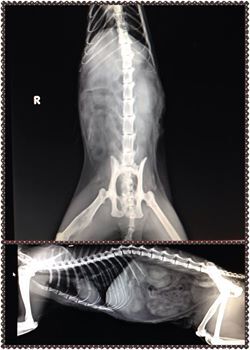

主題: 流浪狗咬傷的孩子加嚴重腎衰、脫水(失溫)、脂肪肝 申請者姓名: 大笨牛 花色: 申請日期: 2014-12-16 23:36:31 申請者部落格: 申請者臉書網址: https://www.facebook.com/profile.php?id=1489838064 所在縣市/合作醫院: 台北市/沐恩動物醫院 治療費用: 24755元 需求人數: 27人 已結案 (2015-02-24 11:54:08) 報名人員: QQ(已付款)、Mao Guai x2(已付款)、Nancy(已付款)、徐凰媛(已付款)、Sam(已付款)、Amberger(已付款)、annawu(已付款)、Cay Way、Cay Way、yymeow(已付款)、Po-Lin Chen(已付款)、Catbask x2(已付款)、陳昱先(已付款)、sally x2(已付款)、Wan Rung Teng(已付款)、Amber Chung(已付款)、Ryoka Yu(已付款)、ERic YU(已付款)、Luis(已付款)、Mickey(已付款)、Vinnie Hsu(已付款)、Yachun Zhan(已付款)、Wu Jun Chieh x2(已付款)、芳芳(已付款)、Princess Kuo(已付款)、 候補人員: 動物病情說明: 動保處打電告知有民眾撿到我TNR 的貓咪,告知我儘快領回,不然她會死掉,馬上驅車前往板橋動保處,眼前景象嚇我一跳,貓咪已經被麻醉,但沒有做任何傷口處理,只打了抗生素,叫我帶出醫療,只有說救來的民眾說貓咪本有送三重就近醫院醫治,但金額他無法負擔,所以才送動保處。

花媽被流浪狗咬傷

還有嚴重的黃疸、失溫(脫水)腎衰

花媽的另一顆還ok的腎臟(有一顆已經沒作用了)已經開始腫大發炎

早上醫生來電告知花媽的白血球飆到9萬多

她比較ok的那顆腎也已經停止工作了